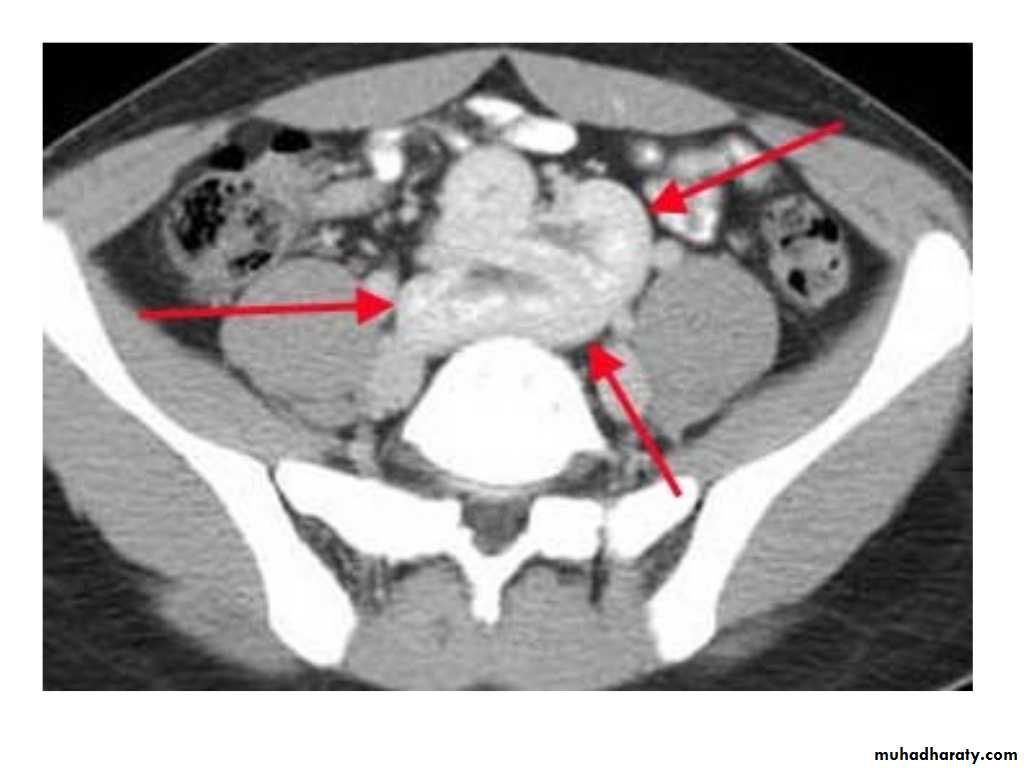

IVU shows

1. The kidneys at low position .2.Close to the spine with long axis parallel to the spine

3. Malrotation manifested by medially directed calyces.

4- The renal pelvis and ureters are anterior and lateral in position.

5- Hydronephrosis and calculi highly associated.